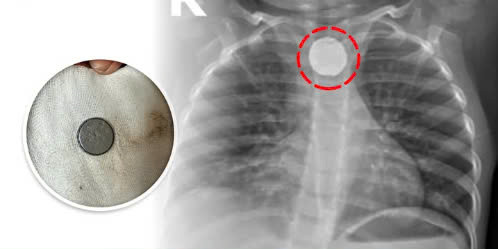

Tại bệnh viện, bệnh nhi nhanh chóng được các bác sĩ thăm khám, chỉ định chụp X-quang cổ, ngực và bụng phát hiện dị vật ở 1/3 trên thực quản.

| Dị vật pin cúc áo nằm trên thực quản của bệnh nhi. Ảnh BVCC |

Các bác sĩ chuyên khoa Tai mũi họng, Tiêu hoá tiến hành nội soi đường tiêu hoá, gắp ra được một viên pin tròn, đường kính 2 cm, ghi nhận loét nông niêm mạc thực quản do hoá chất rỉ ra từ viên pin rất độc hại. Bệnh nhi được đặt ống thông mũi hỗng tràng để tránh nguy cơ chít hẹp đường tiêu hoá và được điều trị thêm thuốc băng niêm mạc đường tiêu hoá, kháng sinh, dịch truyền dinh dưỡng.